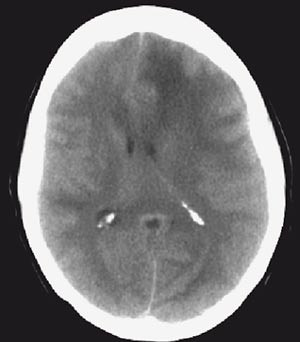

I løpet av første døgn i sykehus utviklet pasienten afasi og økende parese i høyre sides ekstremiteter. Natt til femte døgn i sykehus tilkom redusert bevissthet, og i løpet av noen få timer ble hun komatøs med blodtrykksstigning til 230/130 mm Hg og bradykardi (40 slag per minutt). Hun utviklet venstre oculomotoriusparese som tegn på truende herniering. Cerebral CT viste betydelig ødemutvikling med utslettede sulci over konveksiteten, midtlinjeoverskytning mot høyre og nesten global okklusjon av de basale cisterner (fig 2).